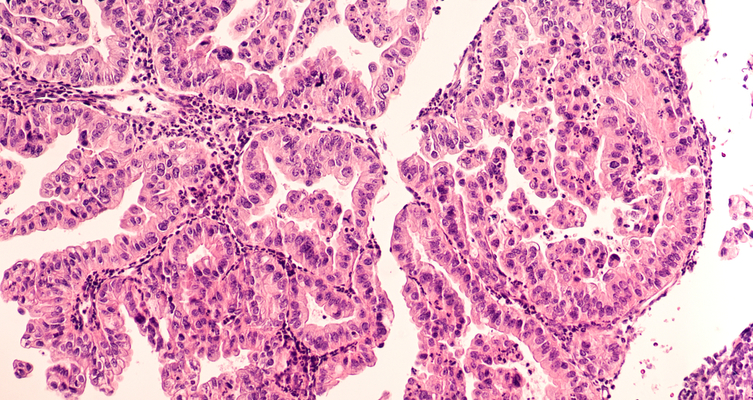

Do I Have Ovarian Cancer Quiz : 'No' to Ovarian Cancer Screening: Harms Outweigh Benefits / Here are a few questions that you could attempt to answer to check your knowledge on ovarian cancer.. Ovarian cancer begins in the ovary, a female reproductive organ that produces an ovum (egg). Ovarian cancer, or cancer of the ovaries, is one of the most common types of cancer in women. Genes are responsible for some cases of ovarian cancer.1/10. This outer layer of cells is called the germinal epithelium of the ovary. Ovarian cancer refers to any cancerous growth that begins in the ovary.

Ovarian cancer refers to any cancerous growth having its origin in the female organs called ovaries, which are capable of producing eggs. The importance of early diagnosis is clear: Ovarian cancer begins in the ovary, a female reproductive organ that produces an ovum (egg). About 90% of women live 5 years. Your doctor will likely do a pelvic exam to check for an enlarged ovary or signs of fluid in the abdomen (which is called ascites).